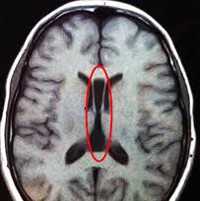

Фото мозга в разрезе и на МРТ ребенка с диагнозом агирия

![синдром Уокера-Варбурга]()

- Агирия (лиссэнцефалия) - аномалия формирования коры головного мозга, при которой извилины недоразвиты, слабо выражены, либо отсутствуют, архитектоника коры нарушена. Внешний вид головного мозга ребенка идентичен внешнему виду мозга плода на 3-4 месяце пренатального периода. Агирия является тяжелой формой лиссэнцефалии. Может быть как идиопатическим заболеванием, так и сопровождать другие патологии (синдром Миллера-Дикера, синдром Нормана-Робертса, синдром Уокера-Варбурга, врожденную мышечную дистрофию Фукуямы).